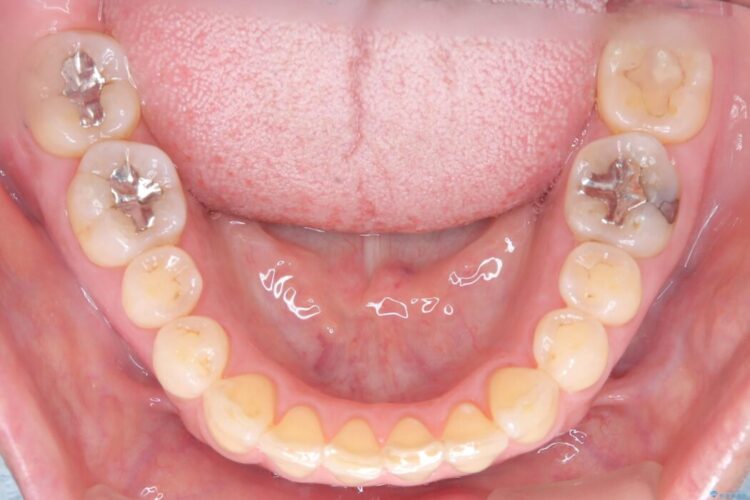

前歯のガタつきが気になるとご来院された患者様です。

精密検査の結果、抜歯は不要、わずかなスペースを確保することで歯並びを整えられると診断しました。

ワイヤー矯正ならではの確実な歯のコントロールにより、当初の計画通り約1年という短い期間で、前歯のガタつきが解消。見た目が美しく整っただけでなく、清掃しやすい機能的な歯並びを獲得していただけました。